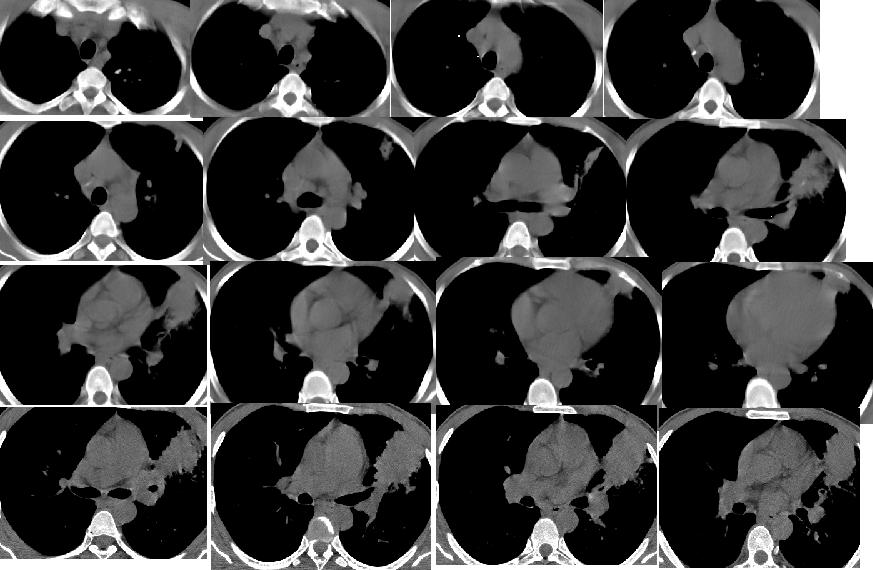

以下是引用随光逐影在2008-9-4 22:33:00的发言:[br]考虑左肺上叶舌段周围型肺癌并阻塞性肺炎,左肺门及纵隔淋巴结转移。

以下是引用huangxun4321在2008-9-4 22:06:00的发言:[br]肿块不规则,内可见坏死液化,边缘可见毛刺征,周围可见晕征,胸膜牵拉征,临床有痰中带血,考虑周围型肺癌可能性大